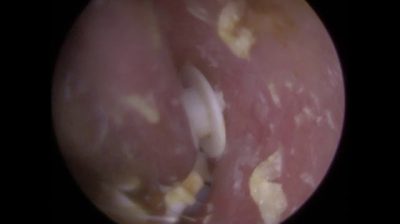

22 hearing filters removed from a patient’s ear

This foreign object removal procedure is performed by UK pioneer and world leading endoscopic ear wax removal specialist Mr Neel Raithatha (Consultant Audiologist) aka ‘The Wax Whisperer’ at his clinic in Oadby, Leicester, UK.

The foreign object removal procedure in this video, which were hearing aid wax filters that kept falling off the hearing aid into the ear canal, utilities the iCLEARscope®, Zoellner suction probe and Crocodile forceps. The client was referred to ENT on the NHS but the waiting time for a minimum 3 months. For obvious reasons the client wanted to have the hearing aid wax filters removed as soon as possible and was referred to myself from another Audiologist.